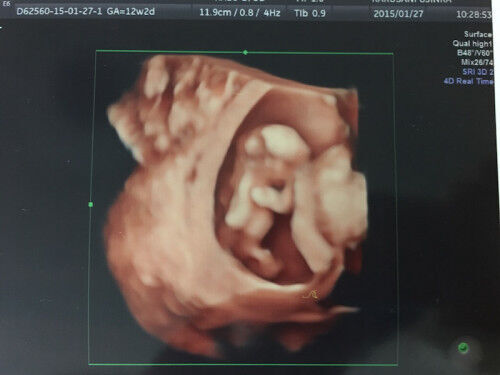

4dエコーって何 2d 3dエコーとどう違うの